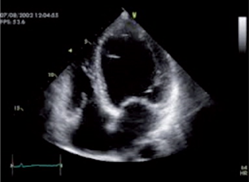

Control echocardiogram is performed

We can appreciate the amazing size left ventricle and normal global and segmental contractility with normal left ventricular ejection fraction (75%). Previous 10%. In addition, the patient was asymptomatic from the cardiological point of view. In such a way that all the medication that was started for the treatment of dilated cardiomyopathy was suspended, such as: Sacubitril/valsartan, furosemide, aldactone, ivrabadine, metoprolol, oral anticoagulants. The only treatment for her arterial hypertension was left with candesartan 16 mg per day and rosuvastatin 40 mg at night for mixed dyslipidemia. The following 6 patients 5 are male with ages: 28, 33, 35, 85 and one female: 95 years of age whose ejection fractions were similar 18, 17, 16 and 15% respectively and their evolution is similar to that of First case with an echocardiographic and clinical evolution to total normality. All patients currently lead a completely normal life.1-3